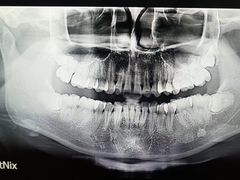

• -上海市徐汇区口腔医院

排骨糯米 | 25-07-26

报错